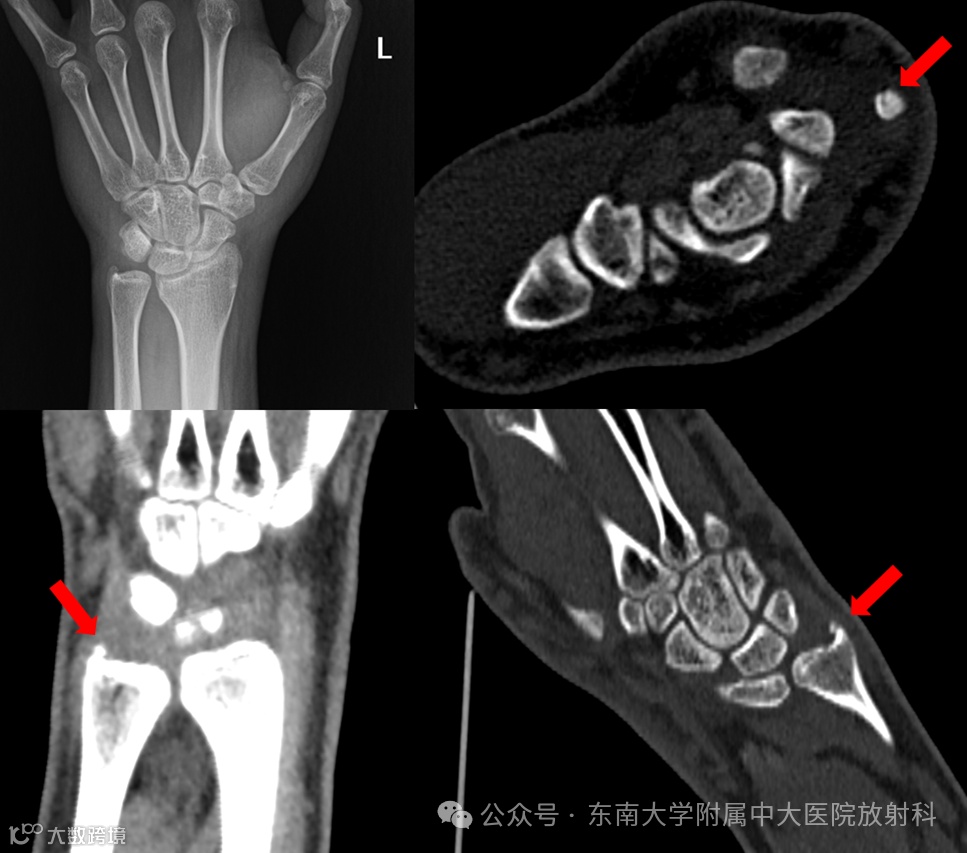

病例1

男 ,17岁

主诉:被撞伤致左腕关节肿痛半小时

病史:约半小时前患者骑车时被撞倒地,致右肘、左腕、双侧膝关节多处皮肤擦伤伴局部肿痛,受损关节活动稍受限,前来就诊

专科检查:左腕关节肿胀,局部压痛,左腕关节活动稍受限

影像号:3557176,2025-12-09,左腕关节正侧位X线、左腕关节CT平扫;影像号:3559976,2025-12-13,左腕关节MRI平扫

影像学表现